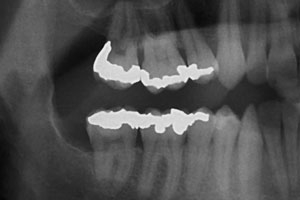

After 7 months of orthodontic extrusion, radiography showed a significant reduction in the size of the cystic cavity and the apposition of new bone on the distal surface of the second molar (Fig. 5). As the roots of the impacted tooth were now farther from the mandibular canal, it was decided to deactivate the cantilever and extract the third molar after a 3-month retention phase. During surgery, the cyst was also completely removed. Tooth extraction was simple, and healing was uneventful with no neurologic damage. At 2 years follow up, probing pocket depth was 2 mm on the lingual side and 3 mm on the buccal side of the distal root surface of the second molar; a large amount of crestal bone apposition was detected on the radiograph and crestal bone loss was now only 2 mm — an 87.5% reduction in the extent of the bone defect compared with the initial observation (Fig. 6).

Figure 6: Panoramic radiograph at the 2-year follow -up. Only a minimal bone defect remains on the distal surface of the second molar.

After 7 months of orthodontic extrusion followed by a 3-month retention phase to ensure adequate bone maturation,11 a significant reduction in the cystic cavity had occurred as well as new bone apposition on the distal surface of the second molar. At a 2-year follow-up appointment, clinical and radiographic examination confirmed that only a minimal bone defect remained on the distal surface of the second molar (Fig. 6). Thus, combining marsupialization with orthodontic extraction enhanced bone apposition, decreasing the risk of periodontal breakdown at the distal surface of the second molar and increasing the resistance of the mandible. The latter was of utmost importance as the patient was a windsurfing instructor and, thus, prone to pathologic fracture.